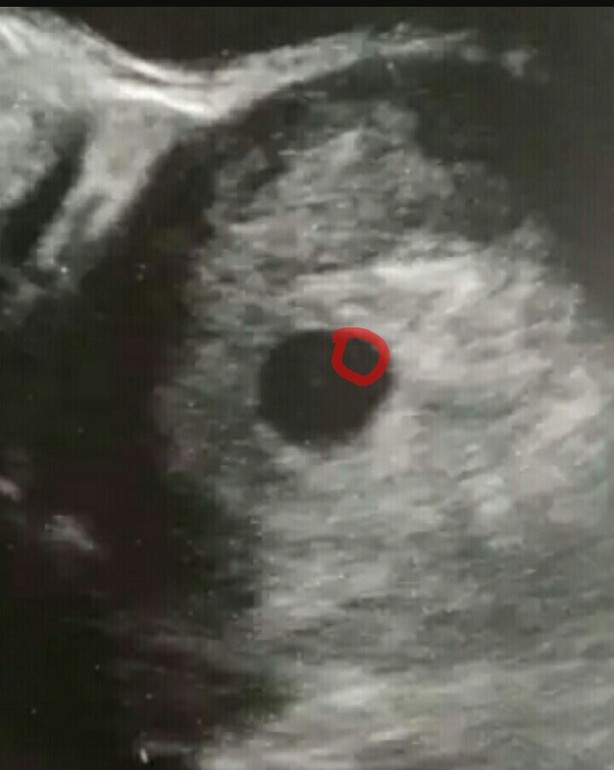

а я на фото вижу эмбрион🤔 червячек такой

Он должен быть круглым🤔

вот что-то кругленькое